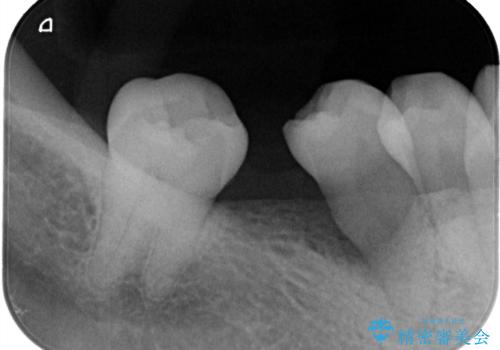

- 右下奥歯の不安定な状態を主訴にご来院されました。精密検査の結果、右下5番の歯周病が進行しており、歯周組織の再生治療が必要と判明。また、その奥にある7番の歯が傾いていたため、6番の部分にインプラントを入れる前に、部分矯正で7番を理想的な位置に起こす計画を立案しました。これら一連の治療を経て、最後に失われた6番の部分にインプラントを埋入し、機能的な咬み合わせを再建することを目指しました。

右下5番の歯周組織再生治療: まず、歯周病が進行していた5番に対して、再生療法を行いました。これにより、失われた骨や歯周組織の回復を促し、歯を安定させることができました。

右下7番の部分矯正: 次に、傾いていた7番を垂直に起こすための部分矯正を実施しました。これにより、6番に入れるインプラントのためのスペースが確保され、咬み合わせの軸が安定しました。